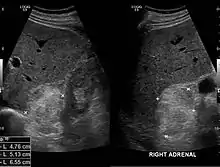

الورم الشحمي النقوي (بالإنجليزية: Myelolipoma) هو ورم حميد يتكون من نسيج دهني والخلايا المكوِّنة للدم بنسب مختلفة.[1] قد يظهر في الغدة الكظرية[2] أو خارجها.[3]

في الغالب لا يسبب الورم أعراضًا ظاهرةً، ولا ينتج أي هرمونات كظرية، وقد يكتشف خلال إجراء فحوصات لأمراض أخرى.[6]

في الغالب لا يظهر الورم من خلال الأشعة المقطعية أو أشعة الرنين المغناطيسي، وقد يظهر عن طريق التصوير الشعاعي بالأشعة السينية.

قد يتم أخذ عينة بالإبرة لفحصها مجهريًّا.[1]